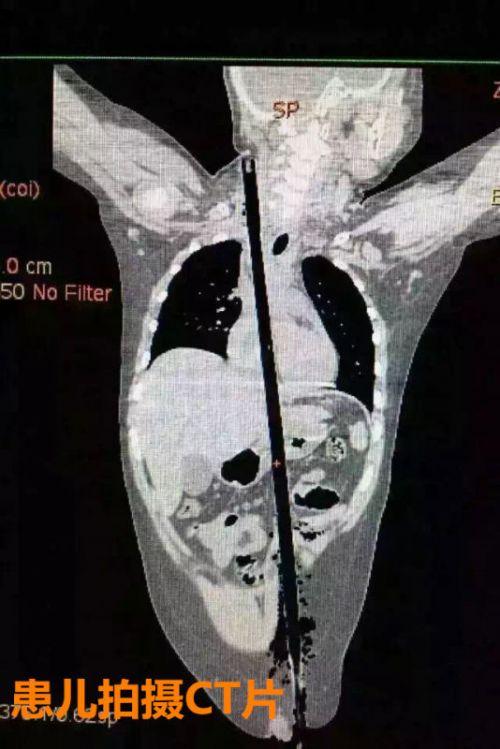

患儿拍摄CT片

据相关知情人介绍,受伤男童24日晚在家中与小朋友一块儿在墙头上玩耍时,一不小心从高墙上跌落到了邻家花圃中,让人触目惊心的是,该男童正好跌到了花圃中的一支长约63厘米,直径约1.5厘米的竹棍上,竹棍自孩子的左侧大腿根部直接插入腹腔并入胸腔直至右侧颈部。

市儿童医院组织专家团队对孩子的病情进行检查、评估后发现,竹棍由患儿左侧大腿根部插入,经腹腔穿透胃、肝脏、膈肌入胸腔,并穿透患儿心脏,经胸腔入颈部,此刻不能拔除竹棍,因为去除竹棍会导致心脏、肝脏破裂大出血导致休克,危及性命。

由于竹棍自心脏的右心房膈面穿入心脏,并由右房近左房顶处穿出心脏,经右胸顶刺入右颈部,右心房破口处紧邻右冠状动脉,幸运的是胸腔内大血管无损伤,在体外循环辅助下,医护团队异物穿出处锯断异物,将插入心脏内的竹棍截断拔除,修补心脏破损处,向上继续寻找周围组织的游离异物,见异物紧临颈部大血管,经精细手术,终于抽出了异物。整个手术时间花了十多个小时。